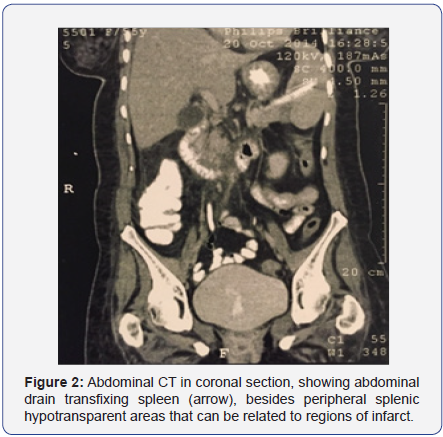

The patient remained hospitalized receiving a conservatory treatment associated with hyperbaric oxygen therapy, showing satisfactory and continuous improvement of her condition and a progressive reduction of the abdominal drain debit, with an improvement of the drained secretion aspect; regardless of showing mild pain on the left upper quadrant and occasional fever (she was receiving antibiotic therapy). She occasionally displayed sudden secretion elimination with a dark maroon color in the abdominal drain of the collecting bag along with a mild and transitory hypotension. The patient was, therefore, submitted to a new total abdomen CT scan (Figures 1 & 2), with the observation of an abdominal drain where its extremities were in the inferior spleen region, not to mention peripheral splenic hypotransparent areas; which may be related to infarct regions. Because of this, the patient was diagnosed with transfixing lesion of the spleen by the tubular drain.